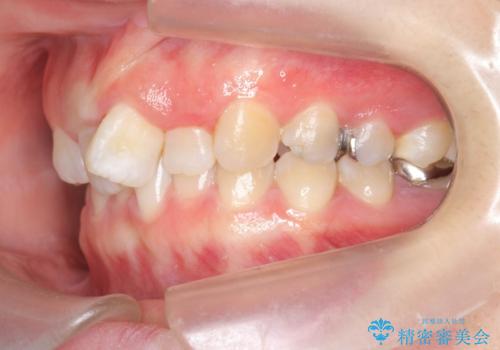

- 大きくねじれた前歯をまっすぐに並べたい。と矯正治療を希望され来院されました。

前歯をきっちり並べるには奥歯の噛み合わせの調整を行い上下の前後的関係を治し、ねじれを取るスペースを確保していきます。

当初前歯だけ治れば良い、という心算で来院されましたが奥歯の噛み合わせも負担が大きく問題の起きやすいことをお伝えし上顎の奥歯をきっちりと後方移動行い噛み合わせの調整を行いました。・